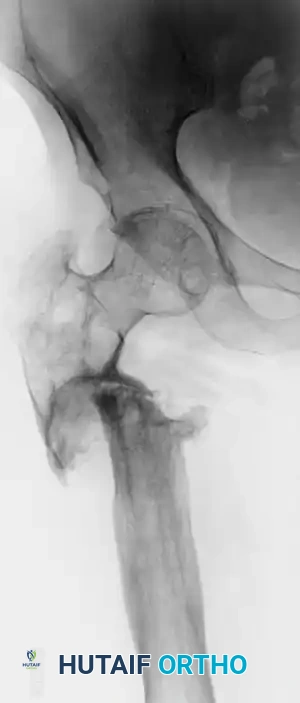

Image

FIGURE 59-10A: Preoperative radiograph of a patient with a recalcitrant subtrochanteric nonunion persisting for 22 years, demonstrating severe sclerosis, deformity, and hardware failure.